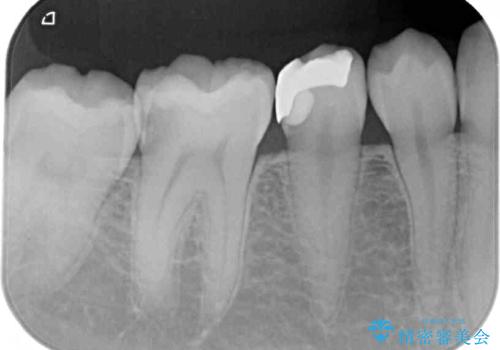

レントゲン写真などから、速やかに処置を行うべき歯が2歯あったため、それぞれセラミックインレーとPGAインレー(ゴールドインレー)にて修復治療を行うこととしました。

どちらの歯も痛みなどの症状はなく、治療後も異常所見なく経過をたどっています。